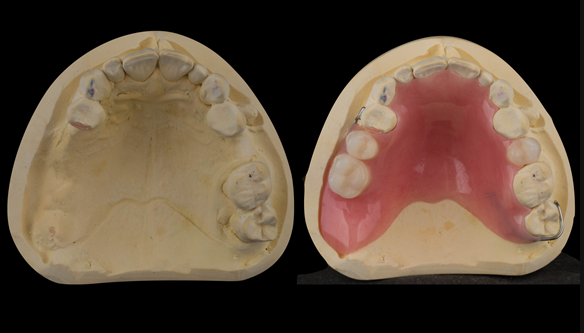

This newsletter describes in step by step detail Angela's transition through immediate partial dentures to crown supported definitive metal based dentures.

The clinical situation and treatment process is shown in detail below with photographs. I (Finlay Sutton) provided the clinical work and Rowan Garstang provided the technical work.